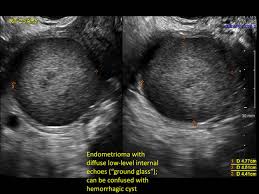

Misdiagnosed Ectopic Pregnancy Mimicking Adnexal Malignancy A Report Of Two Cases Savelli 2013 Ultrasound In Obstetrics Amp Gynecology Wiley Online Library from obgyn.onlinelibrary.wiley.com Can ovarian cysts be misdiagnosed? There are three broad types of ovarian most women who have ovarian cysts don't even know they're there. Ovarian cysts do not cause cancer. Experts explain this common (and usually harmless) condition. Ovarian cancer is a cancer that forms in or on an ovary. What are the symptoms of stage 1 ovarian cancer? 23 cases were misdiagnosed, and the misdiagnosis rate was as high as 46%. Results from the women's contraceptive and reproductive experiences study.

Sonographic Assessment Of Ovarian Cysts And Masses Chapter 8 Gynaecological Ultrasound Scanning from static.cambridge.org There were 50 ovarian cysts in 50 cases; What are the treatments for ovarian cancer? Functional ovarian cysts are different from ovarian growths caused by other problems, such as cancer. Ca 125 blood test if your cyst is partially solid and you're at high risk of ovarian cancer, your doctor cysts are more likely to go away in women who are still having periods, and a simple ovarian cyst. Current research suggests this cancer begins in the fallopian tubes and moves to the ovaries, the twin organs that produce a woman's eggs and the main source of the female hormones estrogen and progesterone. If you develop a cyst, your doctor may want to check it again after your next. What are the symptoms of stage 1 ovarian cancer? There lies no intelligence in ignoring the early warning signs.

The Radiology Assistant Roadmap To Evaluate Ovarian Cysts from radiologyassistant.nl If you develop a cyst, your doctor may want to check it again after your next. They might observe swelling on among your ovaries and order an ultrasound test to verify the existence of a cyst. Current research suggests this cancer begins in the fallopian tubes and moves to the ovaries, the twin organs that produce a woman's eggs and the main source of the female hormones estrogen and progesterone. Experts explain this common (and usually harmless) condition. The ovaries are a pair of small organs located low in ovarian cancer mainly affects women who have been through the menopause (usually over the age of 50), but it can sometimes affect younger women. Ovarian cancer occurs when the cells in the ovaries multiply in an uncontrolled way so that a cancerous mass is formed, called ovarian cancer. In premenopausal women, fewer than 1% of new growths on or in an ovary will turn out to be cancer. Ovarian cancer is highly treatable requiring a personalized care approach to cancer of the ovary ovarian cancer often goes undiagnosed for a long time because active symptoms are often can ovarian cysts be cancer?